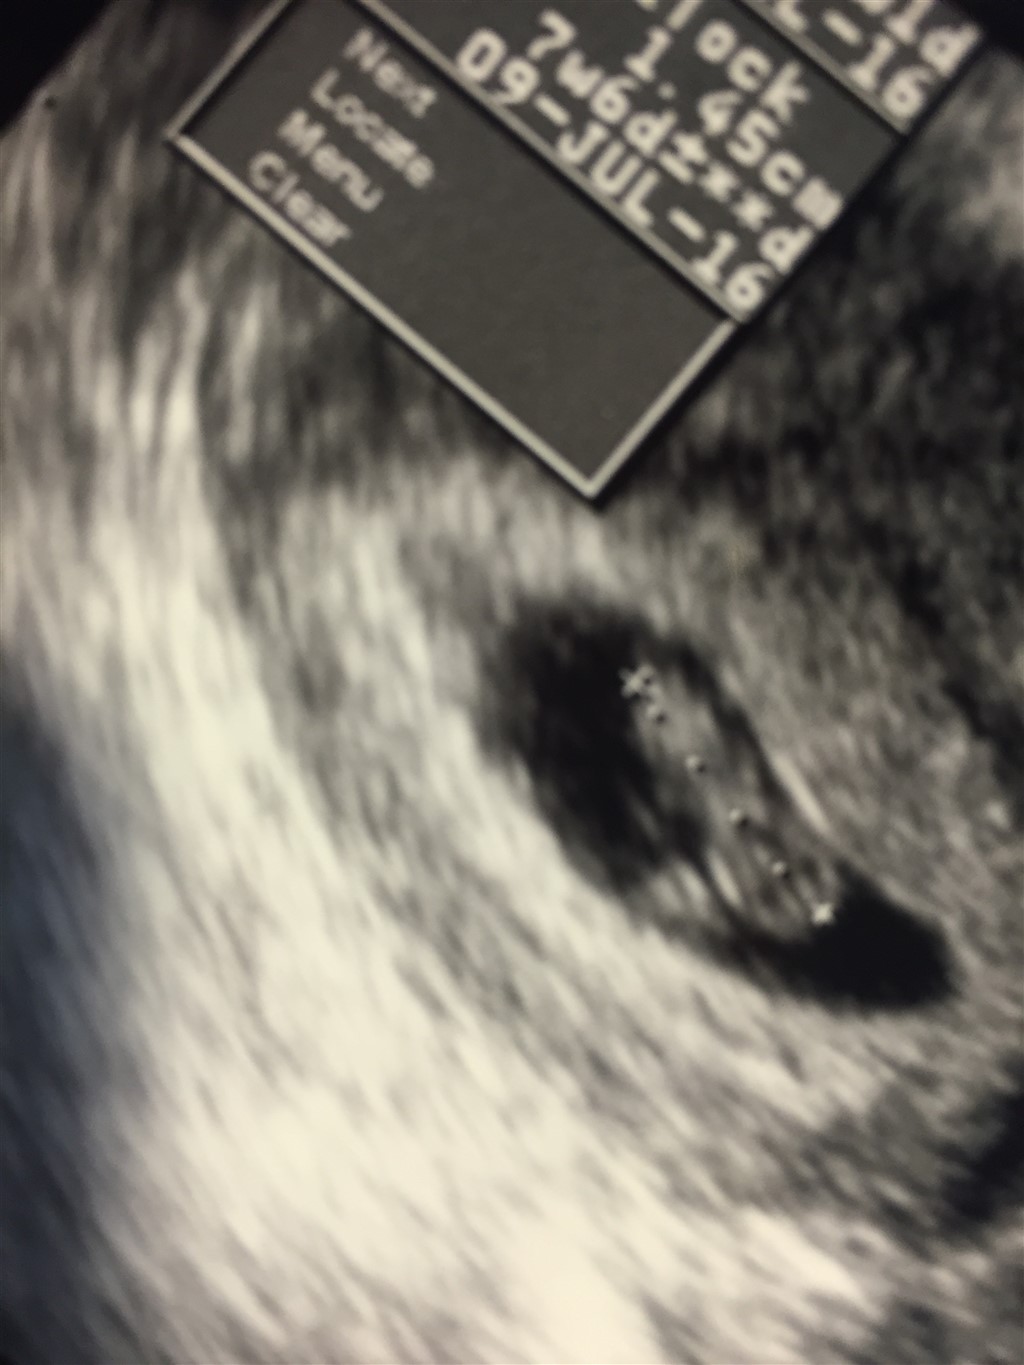

Jeg vil på daværende tidspunkt være 7+6, kan i anbefale det når graviditeten ikke er længere fremme i udviklingen? Kan man se noget på skærmen?

Foregår scanningen vaginalt på dette tidspunkt?